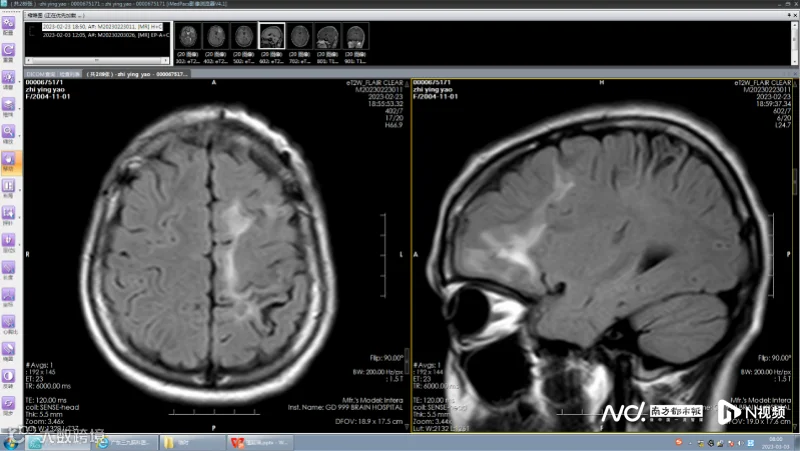

该院医生发现患者左侧额叶存在多发病变,且两次发作症状不尽相同,怀疑是寄生虫感染,“多发脑软化灶实为虫体在颅内爬行产生的损伤。”进一步检查结果提示:裂头蚴IgG抗体阳性;视频脑电图显示:左侧额顶叶多发放电。“患者癫痫发作的根源在于寄生虫对大脑的炎性刺激,造成大脑异常放电。”医生补充道。

脑软化灶实为虫体在颅内的爬行轨迹;(左)从下往上移动,(右)从后往前移动。

通过间隔2周的观察,最终精准定位到寄生虫位于患者左侧额叶前部,并在三维脑上描记了虫体位置。